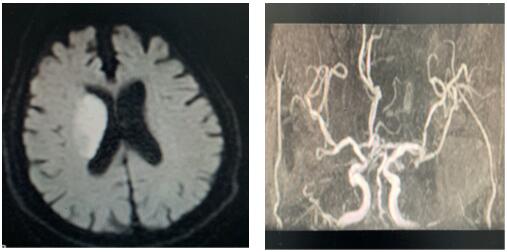

患者治療前影像圖

2020年2月11日,我院卒中中心接到急救電話,一位91歲老人,突發(fā)左側(cè)肢體無力,言語不能,卒中急診李博濤醫(yī)師迅速判斷,考慮急性腦卒中,在NICU王偉偉副主任帶領(lǐng)下,確保疫情防范安全,立即開通卒中綠色通道,卒中護理團隊井井有條做好溶栓工作,謝小攀醫(yī)師嚴密觀察患者生命體征,溶栓效果及不良反應(yīng),治療后左側(cè)肢體肌力恢復4級,達到理想效果。為患者在疫情肆虐中緊急發(fā)病的慌亂心情中,帶來了溫暖與希望。